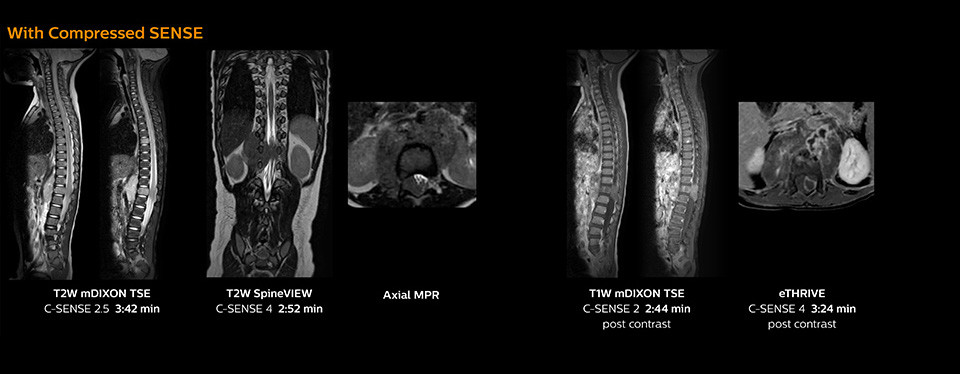

Pediatric spine with neuroblastoma

This 6-year-old patient with neuroblastoma underwent MRI on the Ingenia 1.5T. Compressed SENSE was used to reduce scan time while maintaining the high resolution for 2D mDIXON, 3D SpineVIEW and e-THRIVE in this case. The highly detailed images allowed the radiologist to make a quick and confident assessment of the position of the nerve and the tumor. Especially important for a pediatric patient, is that a shorter scan time also allows us to keep the sedation time as short as possible.

As this was one of the first patients scanned with Compressed SENSE, 3D SpineVIEW was acquired with and without Compressed SENSE to allow comparison. Although the Compressed SENSE sequence was significantly faster, the acquired and reconstructed 3D SpineVIEW images show virtually the same image quality.